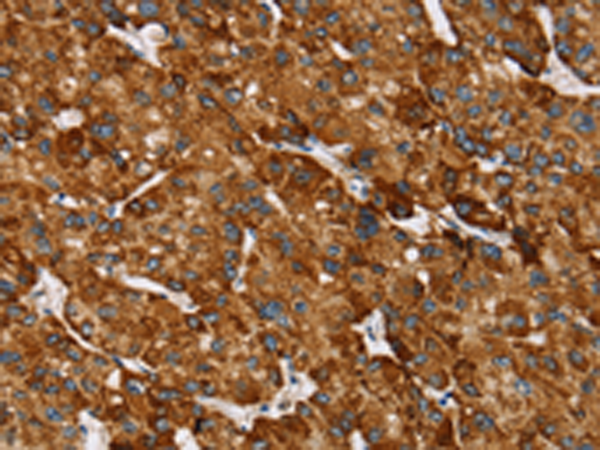

分类: 科研抗体货号: P08686别名: GISP; RELP; REG-IV应用: IHC反应种属: Human